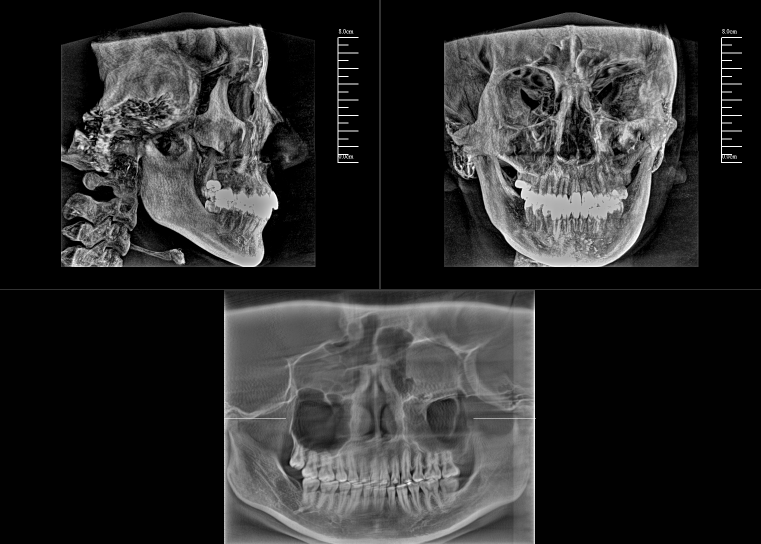

對于口腔內科疾病,牙片和全景片已具有較高診斷效果;但對于牙體牙髓病,2D成像較容易發生影像重疊的情況,無法進一步明確根管和其他周圍組織的三維信息,容易出現漏診或誤診根裂的情況。這就需要三維斷層成像,即數字化口腔CBCT。

數字化口腔CBCT是從三維的角度,即矢狀位、冠狀位和橫斷位來顯示病變組織和正常組織結構,有效的避免了2D圖像固有的缺陷,如正常組織器官的影像重疊,投射角度變化所致的影像扭曲、變形等,大大提高了診斷能力。

數字化口腔CBCT能在十幾秒時間內完成患者口腔掃描,進而生成高精度的三維影像,徹底解決了牙片機、全景機等傳統口腔X射線設備影像重疊、畸變的問題。可以360°全方位立體觀測牙床的骨質密度、牙槽骨本身的高度、寬度等數據,不僅能重建整個顱面區的結構,對頜面骨質結構進行測量,而且還能重建精細的解剖細節。